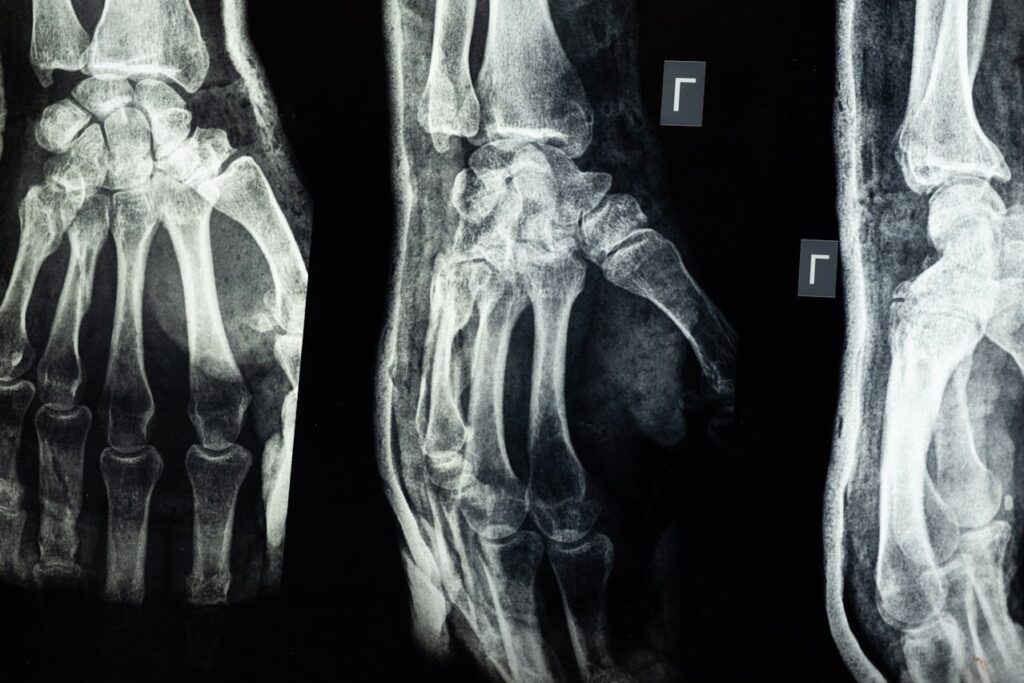

Top 10 pijnlijkste (bot)breuken

Top 10 pijnlijkste (bot)breuken Botbreuken komen vaak voor en kunnen variëren van mild tot zeer pijnlijk. Sommige breuken genezen relatief snel, terwijl andere langdurige pijn en ongemakken veroorzaken. De pijn hangt af van de plaats van de breuk en de mate van schade aan omliggende weefsels. Breuken die belangrijke zenuwen of spieren raken, kunnen ondraaglijk […]